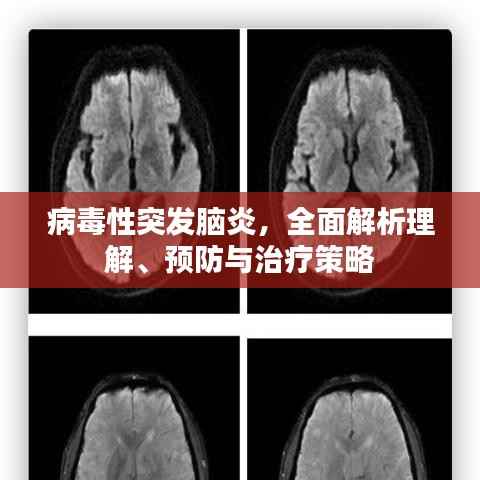

病毒性突发脑炎,全面解析理解、预防与治疗策略

病毒性突发脑炎是一种严重的神经系统疾病,其突然发作并可能引发一系列严重的并发症,本文将详细介绍病毒性突发脑炎的相关知识,包括其成因、症状、诊断、预防以及治疗方法,以帮助公众更好地理解并应对这一疾病。病毒性突发脑炎的成...